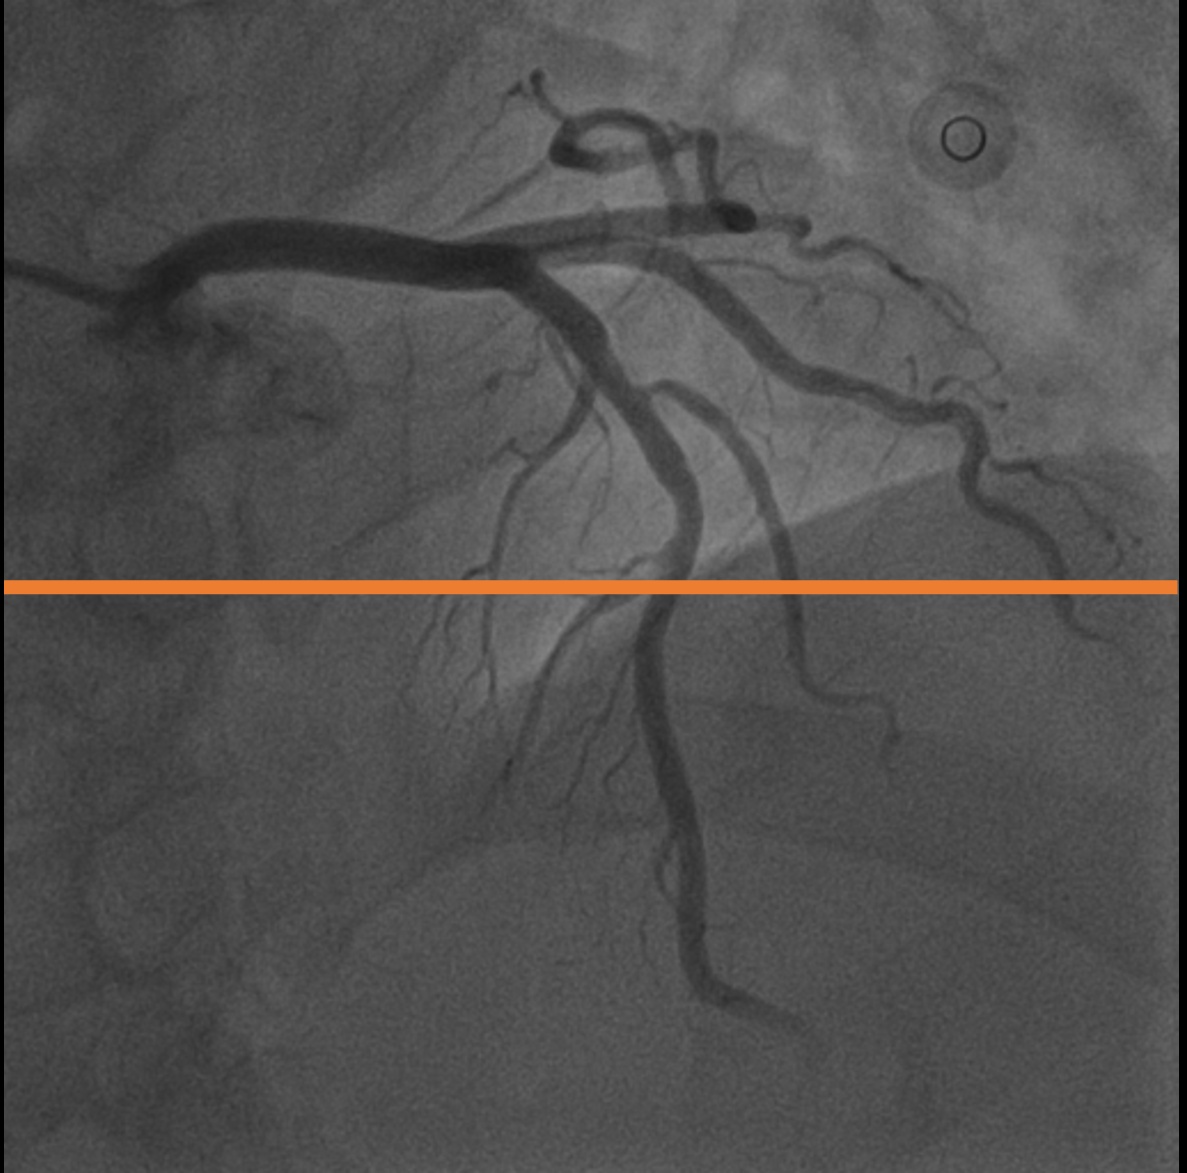

A.2 Temporal Coherency

Our method takes an entire X-ray video as input, thus producing segmentation results with better temporal coherency. Temporal coherency is essential for making medical diagnoses, especially when dealing with blood flow in vessels. Therefore, we conduct visual comparisons between our method and other compared methods by slicing horizontally or vertically and stacking the segmentation results. The results in Figure 11 show our method strikes a better balance between segmentation accuracy and temporal coherency. While other baseline methods either produce false segmentation results or do not maintain consistent prediction along the temporal dimension.